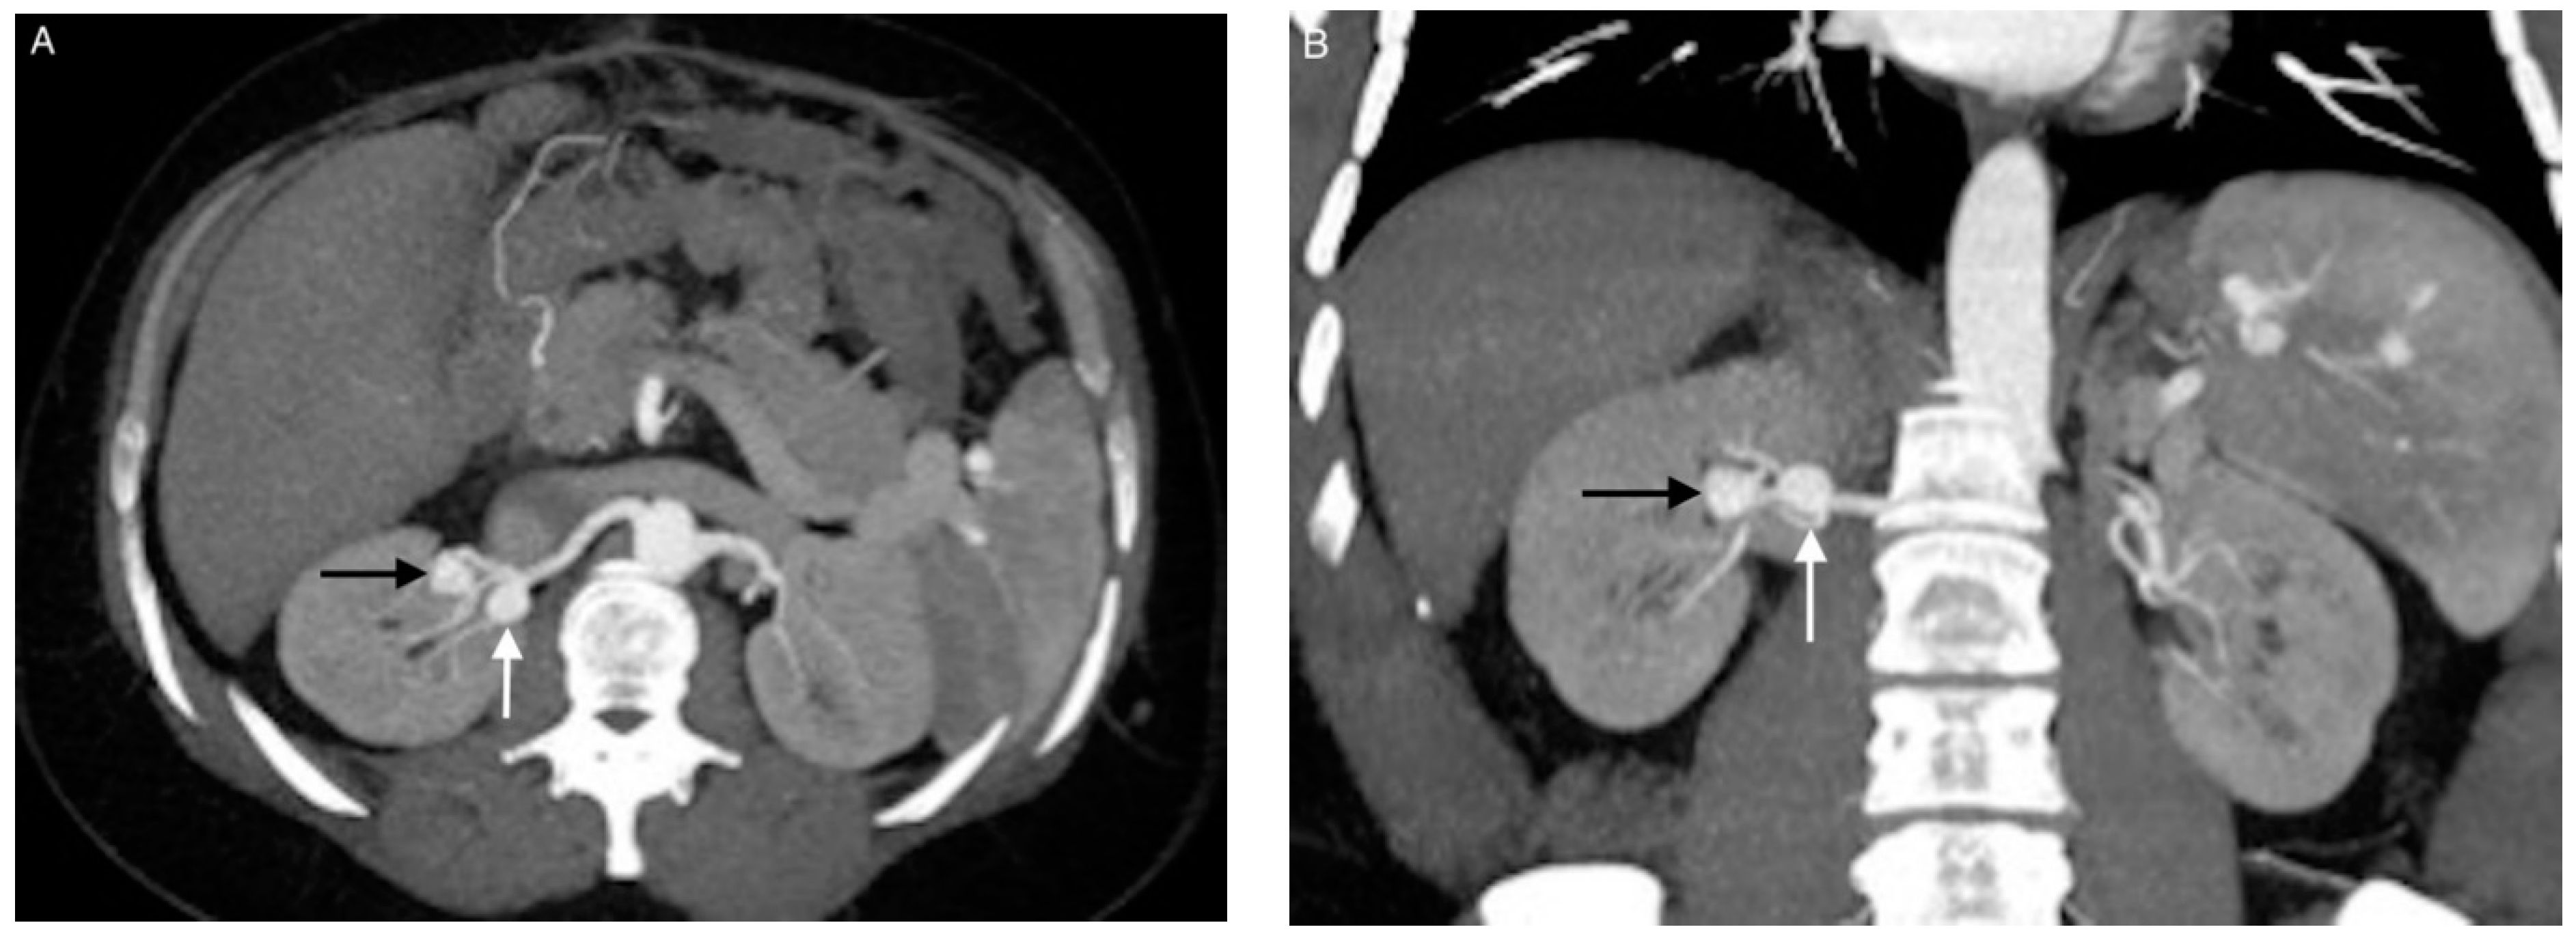

2. Materials and Methods

2.2. Endovascular Procedure

3.3. Coil Embolization and Outcomes